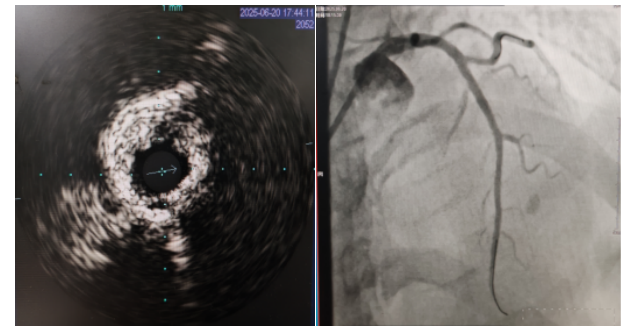

術(shù)中,趙慶禧主任醫(yī)師、雷剛副主任醫(yī)師運用IVUS血管內(nèi)超聲技術(shù)評估,發(fā)現(xiàn)患者前降支、對角支0.1.1型真性分叉病變,前降支近中段嚴(yán)重鈣化、成角并99%狹窄,對角支近段嚴(yán)重鈣化并99%狹窄,傳統(tǒng)冠狀動脈旋磨術(shù)容易引起冠狀動脈穿孔,決定采用沖擊波球囊技術(shù)即血管內(nèi)沖擊波鈣化碎裂術(shù)對患者嚴(yán)重鈣化的血管進(jìn)行介入治療。通過球囊低壓擴張,向血管病變處發(fā)射非聚焦、低能量、脈沖式的沖擊波,對前降支及對角支進(jìn)行了連續(xù)5個周期沖擊波脈沖治療,安全地碎裂淺、深層鈣化,原本看似堅不可摧的環(huán)形鈣化區(qū)逐漸顯現(xiàn)出了裂痕,多處關(guān)鍵位置發(fā)生了斷裂,充分預(yù)處理后于前降支近中段串聯(lián)植入支架3枚,對角支植入藥物球囊,術(shù)后造影見血管病變處狹窄完全消失,支架膨脹完全,貼壁良好,各項生命體征平穩(wěn),手術(shù)非常成功,患者返回心血管內(nèi)科病房繼續(xù)治療,并于4天后順利出院。